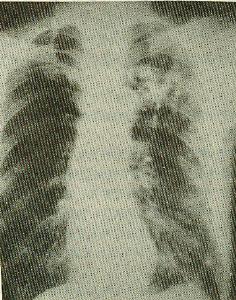

肺气肿(pulmonary emphysema)-慢性阻塞性肺病(copd)